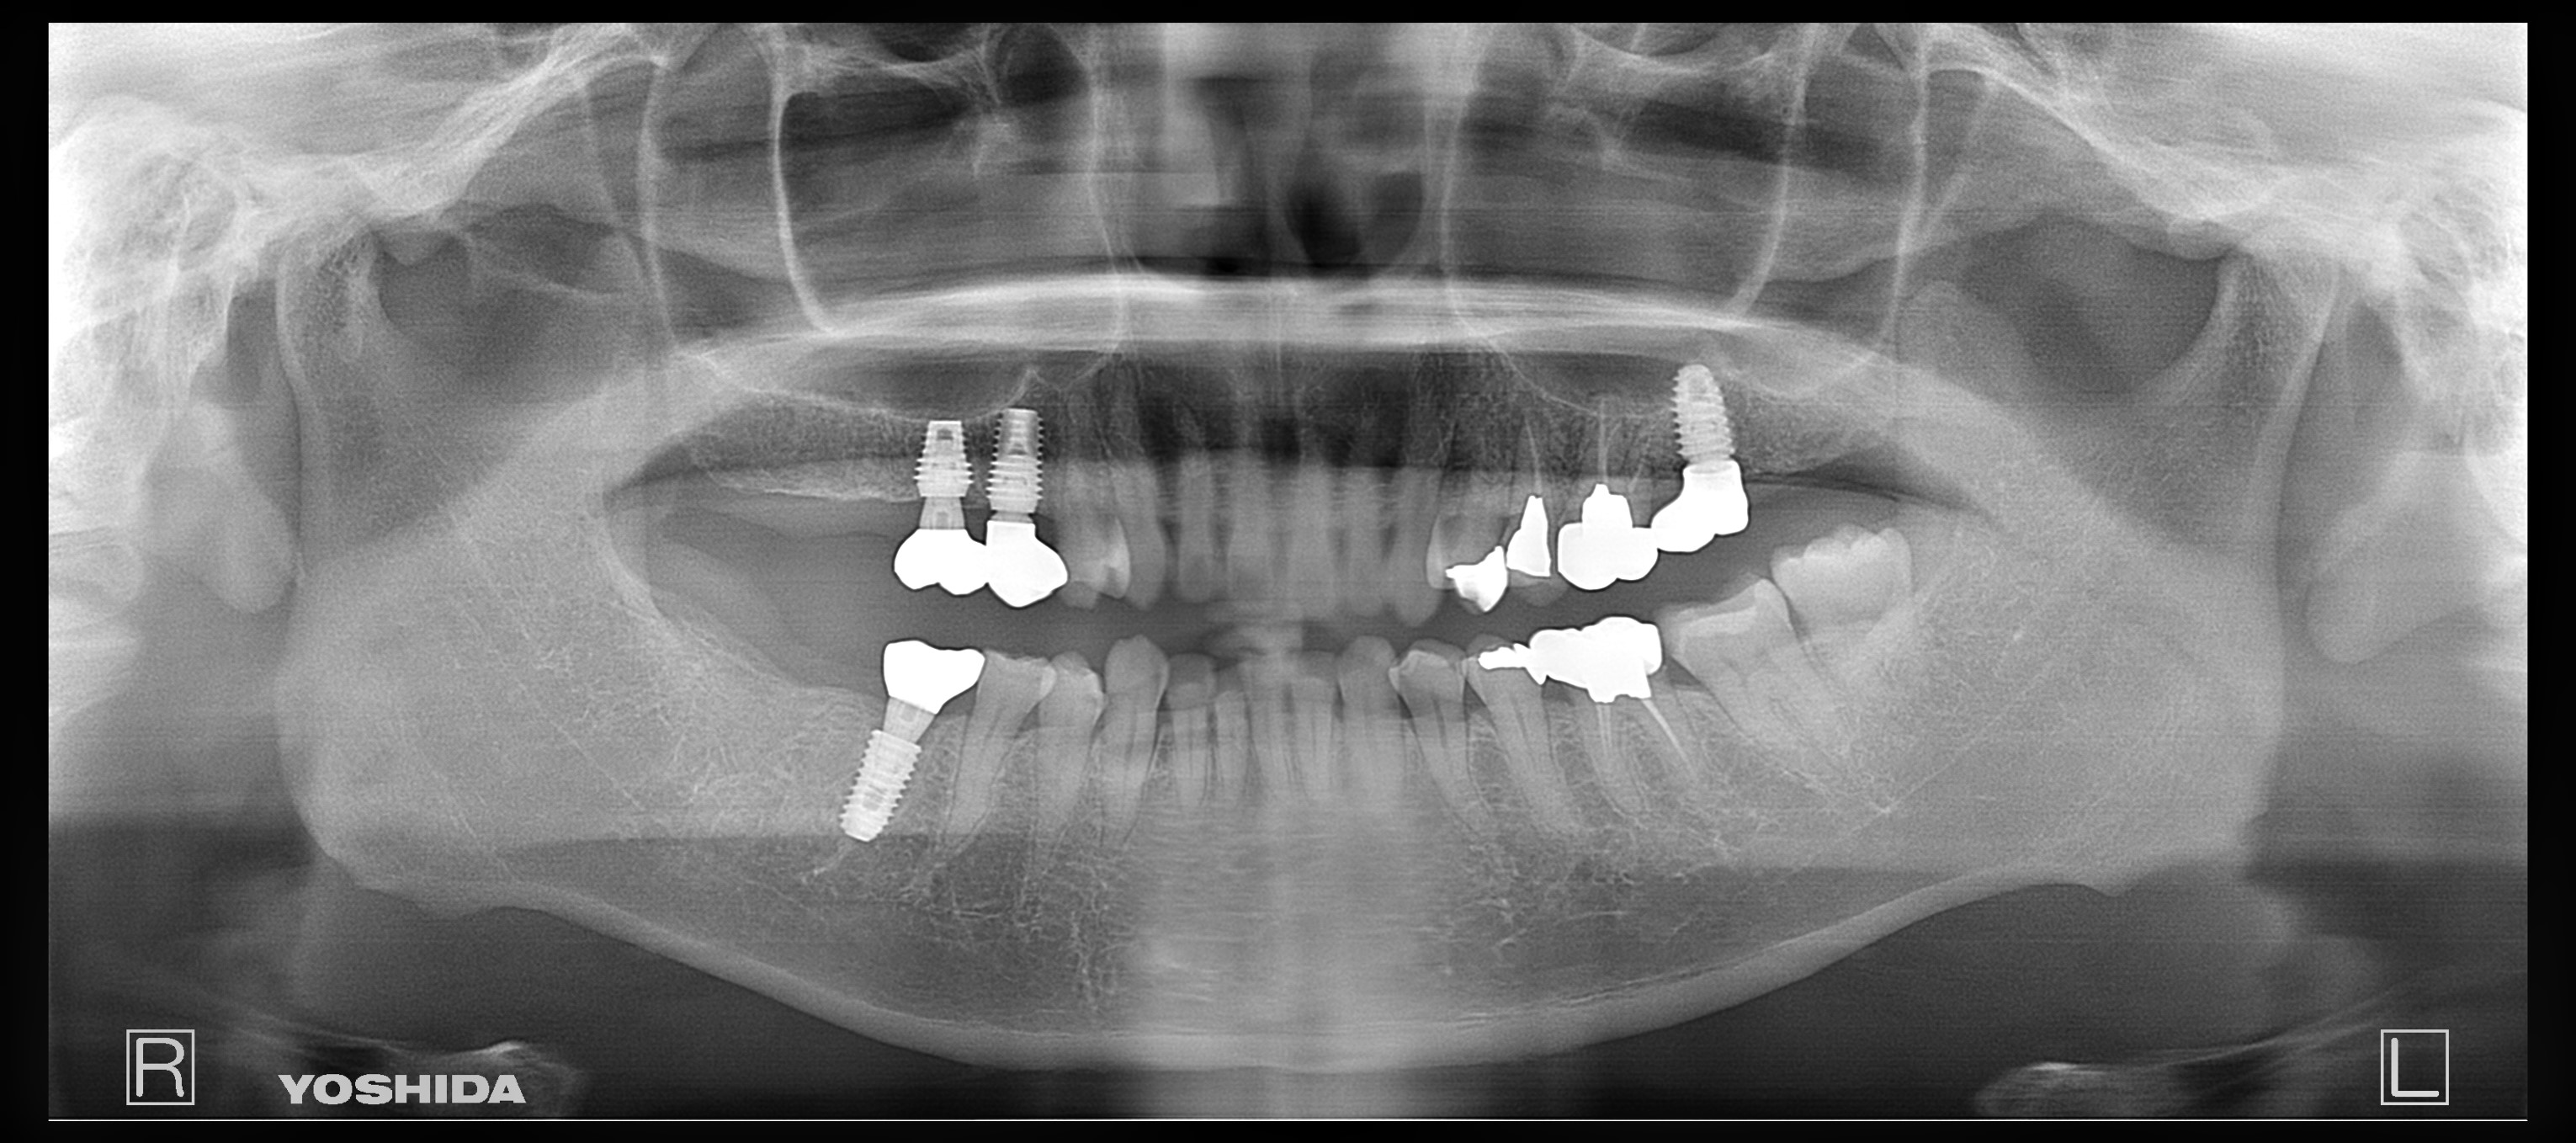

父のレントゲン写真と口腔内を見て、インプラントを入れる位置を一緒に決めて行きました。

右上は歯があるように見えて隣の歯につなげてある被せ物があるだけの状態です。

その右上は骨がないためサイナスリフトという処置を施した後にインプラントを入れる手術をしなければならないのですが、(サイナスリフトは骨を作るだけで6ヶ月待ちます。)

私は水口先生が開発したオステオプッシャーを用いて、骨がないところに骨を足す手術と並行してインプラントを入れる手術を施しました。

左側の入れ歯を入れていたと言っている場所には通常の方法でインプラント治療を、左上の奥歯2本は歯周病でグラグラだったため抜歯と同時にインプラントと治療を行いました。

左側のレントゲンがが最初の状態です。右側がインプラントを入れ、被せ物まで入れた状態のレントゲンです。